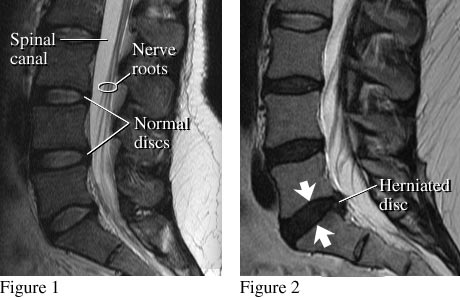

A side view of the lumbar spine shows normal discs, spinal canal, and nerve roots (see figure 1). Nerve roots normally float in the fluid-filled canal. Figure 2 shows a small herniated disc pushing into the canal toward nerve roots.